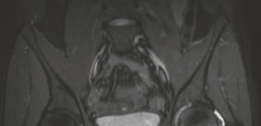

Magnetic resonance imaging (MRI) is highly sensitive for detecting the profound bone marrow edema and adjacent soft tissue inflammation characteristic of osteoid osteomas. While MRI may obscure the nidus itself due to the overwhelming edema signal, it is invaluable for assessing the extent of reactive synovitis, evaluating the integrity of the articular cartilage, and identifying concurrent labral pathology.

Once access to the central compartment is achieved, a systematic diagnostic arthroscopy is performed. The surgeon evaluates the acetabular labrum, the ligamentum teres, and the chondral surfaces of the acetabulum and femoral head. In cases of intra-articular osteoid osteoma, the central compartment often exhibits profound, hyperemic synovitis.